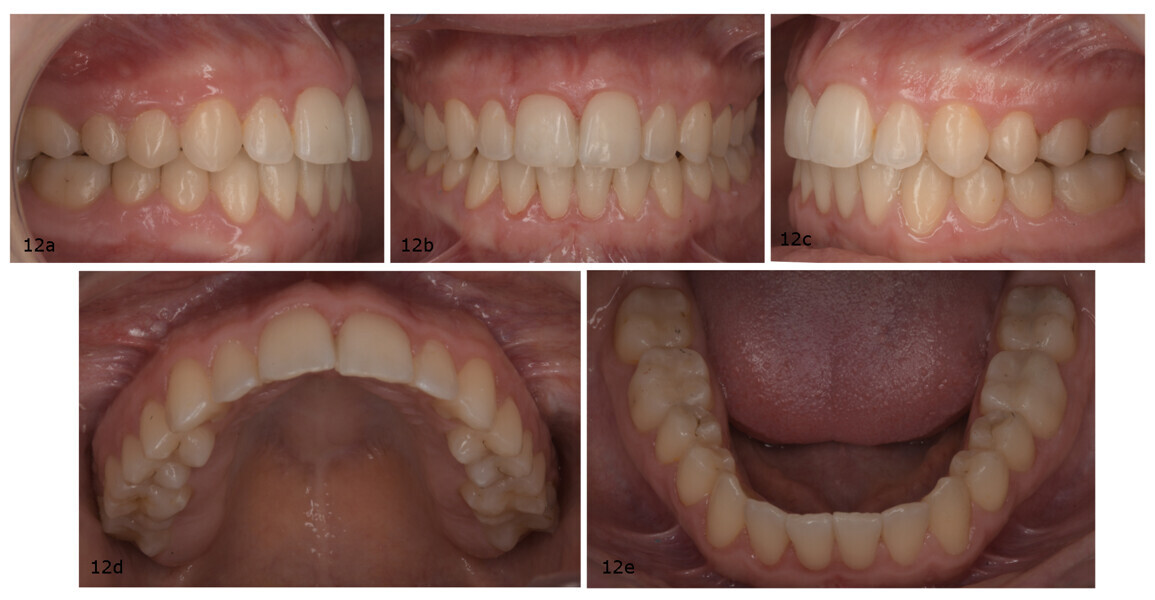

After 18 months of treatment, including the reset phase and refinements, the patient exhibited significant extra-oral improvements, including a more harmonious smile arc, increased incisor display at rest and notable facial profile enhancement driven by effective mandibular auto-rotation (Fig. 11). Intra-orally, the results included Class I molar and canine relationships, proper alignment and levelling of both arches, an ideal overjet and overbite, and coinciding maxillary and mandibular midlines (Fig. 12).